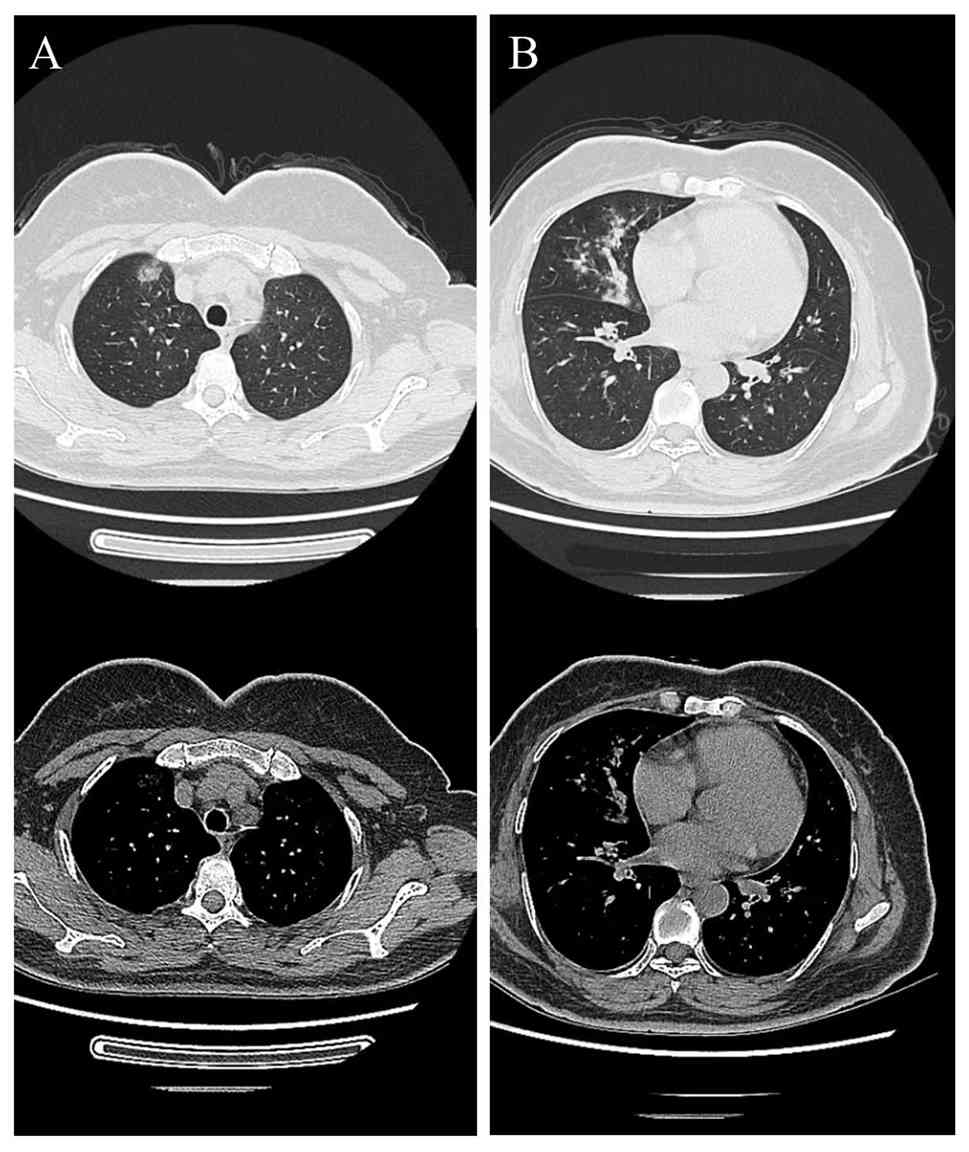

A thorough physical examination was performed, including assessment of vital signs (temperature, blood pressure, heart rate and respiratory rate). Lung auscultation revealed clear breath sounds in the left lung, while a few fine crackles were audible in the right lung fields. No wheezes or rhonchi were noted. No chest tenderness was noted on palpation. Cardiac examination indicated normal heart sounds without murmurs, gallops or rubs and no jugular vein distention was observed. Abdominal examination was unremarkable, with a soft abdomen, lack of tenderness or rebound tenderness, normal bowel sounds (4-5 times/min) and lack of peripheral edema. Lymph node examination revealed no palpable lymphadenopathy in the cervical, axillary or inguinal regions. Neurological and musculoskeletal evaluations showed no focal deficits such as limb weakness and sensory disturbance or joint abnormalities such as swelling and tenderness. A chest CT scan obtained in October 2023 (Fig. 1) indicated patchy and nodular opacities with slightly increased density and ill-defined borders. Test results for 1,3-β-D-glucan, erythrocyte sedimentation rate, C-reactive protein, endotoxin and procalcitonin were within normal ranges (Table I). Legionella pneumoniae, Chlamydia pneumoniae, Mycoplasma pneumoniae, respiratory viruses, coronavirus disease of 2019 and HIV were negative in serological testing. The results for autoantibodies were still negative. Diagnostic tests, including sputum smear and bacterial culture yielded negative results. The patient was diagnosed with community-acquired pneumonia (CAP) and empirical treatment with moxifloxacin was initiated. During hospitalization, moxifloxacin was administered intravenously at a daily dose of 0.4 g. To identify the etiology of the illness, the patient underwent bronchoscopy, which revealed edematous bronchial mucosa (Fig. 2). In addition, the bronchoalveolar lavage fluid (BALF) was analyzed using mNGS. The sequencing of mNGS was performed by Adicon Clinical Laboratories, Inc. (Hangzhou, China). The service report indicated qualified internal and negative controls, host read removal, nucleic acid extraction concentration of 0.11 ng/µl, and library concentration of 29.60 ng/µl. Sequencing QC metrics included 17,699,043 total reads, 1,252,093 non-human reads, and 96.37% Q30. Microbial identification was conducted by comparing sequencing reads to reference microbial nucleic-acid databases, with T. whipplei detected at a total of 19,731 base pairs (bp), a coverage of 2.26%, and an average depth of 1.01X. The report also described a machine learning-based pipeline for error correction, denoising, and exact sequence inference. Antibiotic resistance gene interpretation referenced the CARD database. The results identified T. whipplei (sequence number: 399; relative abundance: 0.08%) as the only pathogen (Fig. 3). After treatment for 8 days, the patient's symptoms improved, with cough resolution and normalization of body temperature. Following discharge, the patient continued oral moxifloxacin at a daily dose of 0.4 g for 1 week and remained in good health. A follow-up chest CT scan in November 2023 (Fig. 4) indicated complete resolution of the bilateral patchy/nodular opacities. A telephone follow-up was conducted after discharge. The patient reported that she was in good health and had not experienced any further complications. The patient declined to visit the hospital for follow-up examinations, including a chest CT scan.

Chest CT imaging of lung lesions upon

admission in October 2023. (A) Lung and mediastinal windows of the

upper lung lobes. (B) Lung and mediastinal windows of the lower

lung lobes. Patchy and nodular opacities with slightly increased

attenuation and ill-defined margins are visible.

Figure 1

Chest CT imaging of lung lesions upon admission in October 2023. (A) Lung and mediastinal windows of the upper lung lobes. (B) Lung and mediastinal windows of the lower lung lobes. Patchy and nodular opacities with slightly increased attenuation and ill-defined margins are visible.